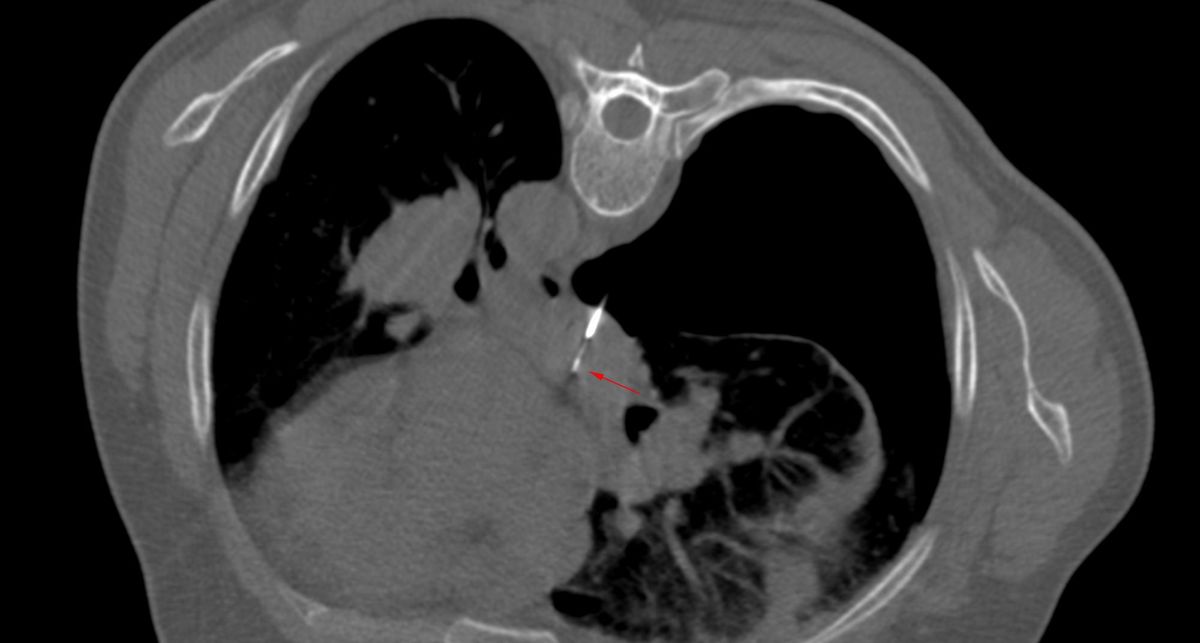

The lung was almost at the midline and there was concern that a transparenchymal approach (A) may be needed as in the last case.

Using an 18G Cook needle, 8 cc of lignocaine was injected in the space between the pleura and foramen in the inter-transverse space (B). Once some space was created then it was advanced with 3 injections of 10-15 cc of a combination of lignocaine and saline (C, D), until the needle tip rested along the posterior margin of the node (D) and then it was pushed into the node (E) followed by the biopsy (F). The gun has a 10 mm throw.

This again takes off my last post on the transparenchymal approach to paratracheal node biopsies. An extrapleural approach with hydrodissection can usually easily be done and while EBUS is commonly used these days, it is not superior to CT guided biopsy, just non-inferior.

Hydrodissection can help push away even lung that extends up to or sometimes across the midline.